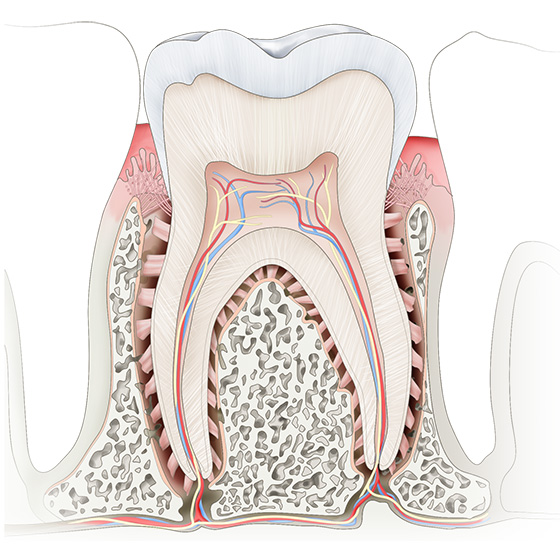

An Overview of Dental Anatomy [Course Number : 500] Vickie Parrish Foster, RDH, MEd

This continuing education course will provide an overview of dental anatomy, including the primary and permanent dentitions, normal facial and intraoral anatomy and the anatomy of the periodontium. This information can be used as a review in order to compare findings outside of the normal.

Anomalies of Tooth Structure (ce651) - Introduction

Anomalies of Tooth Structure [Course Number: 651] Gail F. Williamson, Professor Emerita

The ability to recognize the normal radiographic appearance of the teeth and their component structures is foundational to basic interpretation of intraoral and panoramic radiographic images. It is of equal importance to recognize when the radiographic appearance of the teeth deviates from normal. Dental anomalies associated with tooth structure will be presented to enable the clinician to recognize and identify alterations whether congenital, developmental, or acquired in nature.